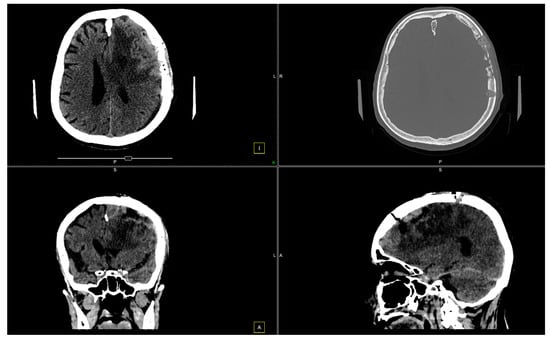

At the 2-month follow-up check, we conducted another CT scan (Figure 7).

Figure 7. CT scan shows left paramedian frontal hypodensity, without contrast outlet.

Due to the high recurrence risk associated with WHO Grade III tumors (Figure 8), routine follow-up with imaging is essential to promptly detect any signs of regrowth.